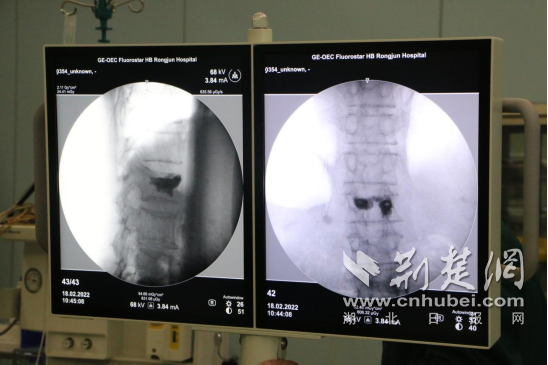

2月18日,手術開始。醫生在患者背部切開黃豆大小的切口,通過穿刺針進入病變椎體內,利用球囊擴張增壓讓壓縮椎體復位,將骨折部位撐開,注入配置好的骨水泥,恢復椎體高度。

手術現場。通訊員供圖

“骨水泥可以增加椎體強度和穩定性,防止椎體塌陷,緩解疼痛。”術后,醫生介紹,“注射過程須透視查看骨水泥的分布情況,防止骨水泥滲漏。”